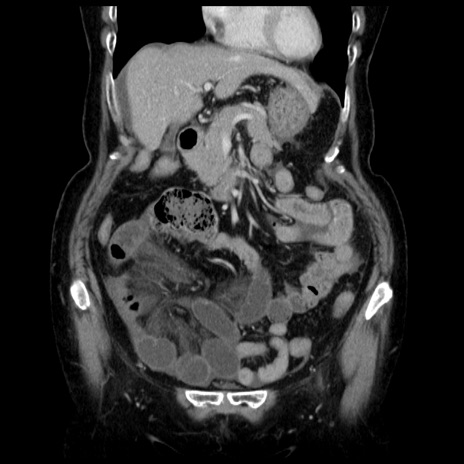

症例13(冠状断像)

【症例】70歳代女性

【主訴】腹痛、嘔吐

【現病歴】15時間程前(昨晩)より腹痛あり。今朝になっても症状の改善なく、嘔吐あり。腹痛も増悪あり、救急外来受診。

【既往歴】子宮癌全摘術後

【身体所見】意識清明、BP 121/72mmHg、P 74bpm、SpO2 100%(RA)、腹部:平坦・軟、腸雑音ほぼ聴取せず。下腹部・心窩部・臍左上に圧痛あり。反跳痛なし。

【データ】WBC 10600、CRP 0.15